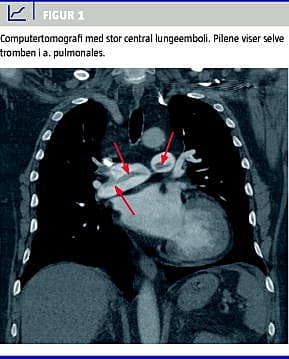

Da patienten fortsat ikke kunne stabiliseres, og klinisk hjertestop med PEA forsat recidiverede, gennemgik man igen de reversible årsager til hjertestop. Det blev vurderet, at den mest sandsynlige årsag var koronar eller pulmonal trombose. Dette til trods for at de ekkokardiografiske fund ikke var oplagte, og patienten ikke længere var hypoksisk (PaO 2 22,1 kPa). På vital indikation gav man derfor under igangværende HLR trombolyse i form af i.v.-givet alteplase 100 mg over 20 minutter, efterfulgt af i.v.-infusion af heparin efter den nationale kardiologiske behandlingsvejledning 2011 [1]. Efter yderligere fem minutters HLR opnåede patienten stabil og sufficient egencirkulation. I løbet af de følgende timer blev hans tilstand stabiliseret, paraklinikken blev normaliseret, og diagnosen central lungeemboli blev bekræftet ved spiralcomputertomografi (Figur 1 ). To uger senere blev patienten udskrevet neurologisk intakt til eget hjem. Ved kontrol tre måneder efter udskrivelse var patienten velrestitueret og havde netop generhvervet sit kørekort.